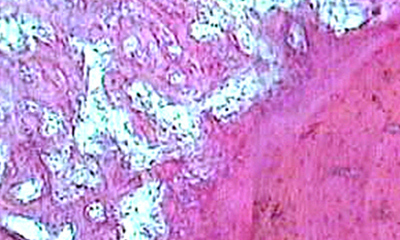

Общее представление о стволовой клетке, ее классификация и источники

Основные закономерности физиологической и репаративной регенерации

Роль стволовой клетки в остеотрепанации

Нарушение остеотрепанации